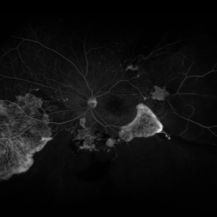

Severe Diabetic Retinopathy, Nonperfusion and NVE

Jun 18 2021 by Kristen Wagner

Optos angiogram of severe diabetic retinopathy, nonperfusion and NVE.

Photographer: Kristen Wagner, COT Tennessee Retina Nashville TN

Imaging device: Optos

Condition/keywords: diabetic macular edema, neovascularization elsewhere (NVE), nonperfusion diabetic retinopathy, proliferative diabetic retinopathy (PDR)